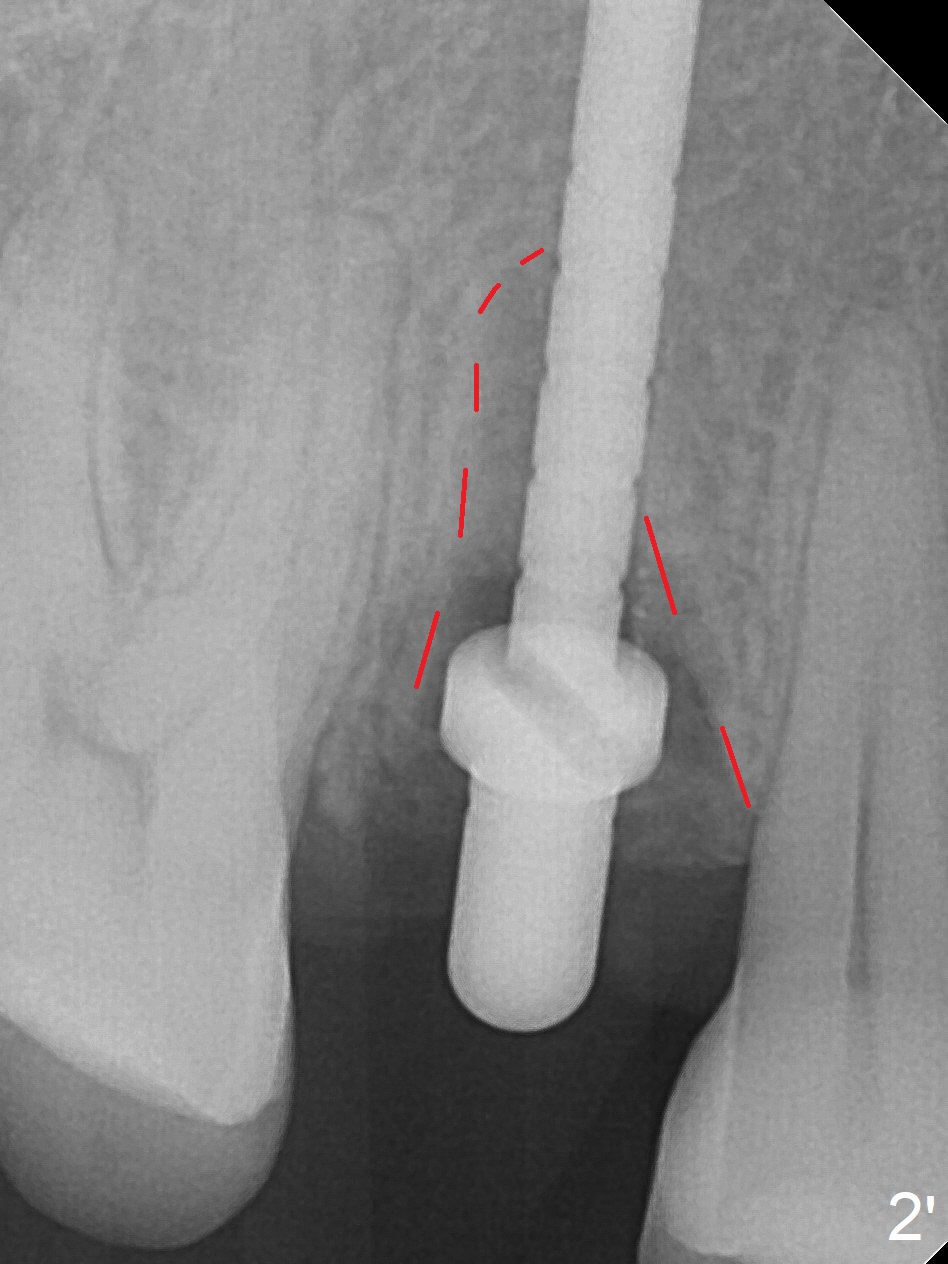

After extraction of residual root at #4 with mesiopalatal subgingival margin (Fig.1), the mesiopalatal crestal bone loss is noted. Instead of the mesial slope, the initial point of the osteotomy is at the mesial and middle (buccopalatally) of the socket bottom (Fig.2, 2'). The initial depth with 2 mm drill is 20 mm (gingival level), while the last drill (3 mm) is used for 17 mm (because of soft bone). When a 3.8x16 mm implant is placed (Fig.3,4), the distal gap of the socket is closed, suggesting that the implant moves to the least resistant area. However, it is favorable to the mesial crestal defect (Fig.4). The buccopalatal position of the abutment (4.5x4(4) mm) is a little too palatal (Fig.5, taken prior to provisional fabrication). The implant seems to have osteointegrated 6 months postop (Fig.6).